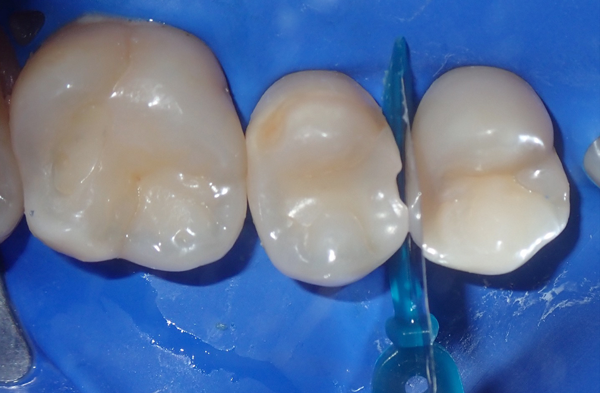

FIG. 3

Removal of carious tissue and old restorations,

creating clean preparations ready for restoration.

Once the old restorations and recurrent caries were removed, pumice and air abrasion were used to remove the plaque and biofilm from the teeth (Fig 3). A Total Etch

Technique was employed to enhance micromechanical retention to enamel and dentin. The process included: